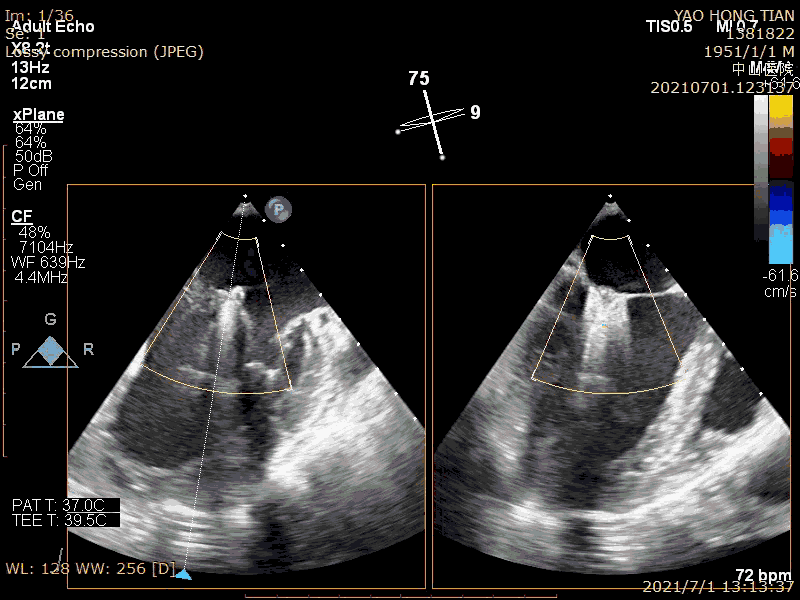

手术过程

半夹合评估效果

完全夹合评估效果

最后效果(轻微反流),最大/平均压:差4/1mmHg